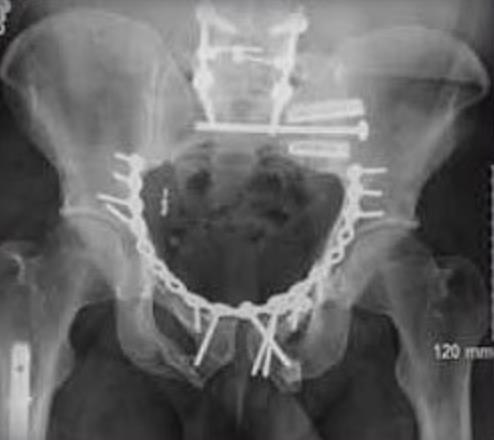

• iFuse-3D is a minimally invasive implant system intended to stabilize and fuse the sacroiliac joint by delivering triangular, porous, fenestrated titanium implants across the joint via a percutaneous approach.

• Triangular-shaped implant profile minimizes rotation, with more than 6× the rotational resistance of a screw, and stabilizes the joint while the porous surface supports long-term fusion.

• Minimally invasive lateral or oblique trajectory through a small incision with percutaneous instrumentation to place triangular implants across the SI joint.

• Triangular implants differ from cylindrical screws by engaging osseous walls with an interference fit that improves rotational stability for SI fixation.

• The geometry demonstrates more than sixfold rotational resistance compared with a screw.